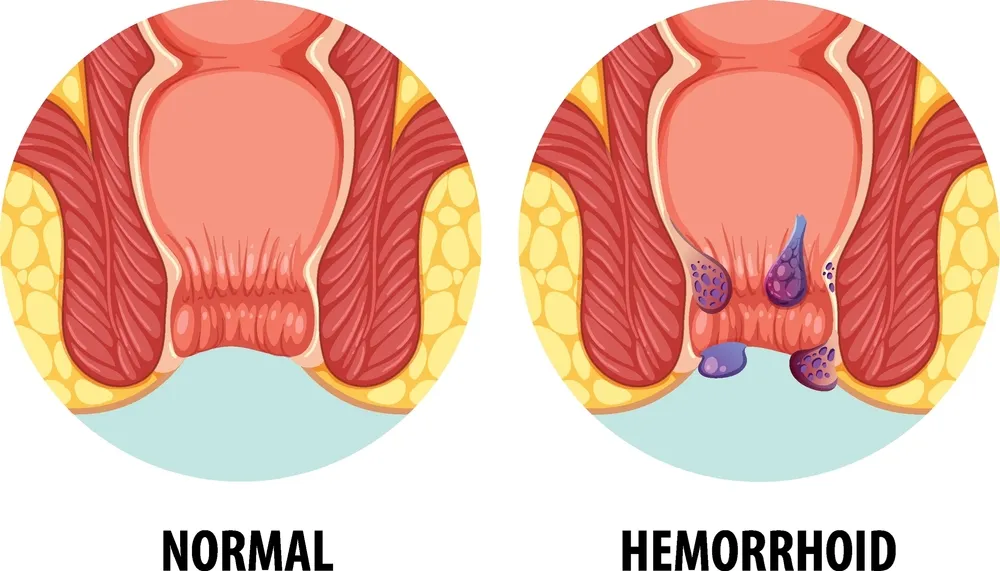

۱. بواسیر یا هموروئید

بواسیر یکی از شایعترین اختلالات نشیمنگاهی است که در نتیجه التهاب و گشاد شدگی عروق وریدی در کانال مقعد ایجاد میشود. هموروئید ممکن است داخلی یا خارجی باشد و علائمی مانند خونریزی هنگام دفع، درد، خارش و احساس توده در مقعد ایجاد کند.

بواسیر یا هموروئید (Hemorrhoids) یکی از شایعترین بیماریهای ناحیه مقعد و دستگاه گوارش انتهایی محسوب میشود که میلیونها نفر در سراسر جهان را درگیر کرده است. این بیماری در نتیجه تورم، التهاب یا گشاد شدگی غیرطبیعی عروق وریدی در ناحیه کانال مقعد ایجاد میشود و میتواند با علائمی چون درد، خونریزی، خارش، سوزش و احساس توده همراه باشد.

انواع بواسیر و تفاوت آنها

بواسیر بهطور کلی بر اساس محل قرارگیری عروق متورم و علائم بالینی به دو نوع اصلی تقسیم میشود:

۱. بواسیر داخلی (Internal Hemorrhoids)

این نوع از بواسیر در داخل کانال آنال، بالاتر از خط دندانهای (dentate line) قرار دارد و معمولاً در مراحل اولیه بدون درد است، اما میتواند با خونریزی روشن هنگام دفع همراه باشد. در برخی موارد، این نوع بواسیر از مقعد خارج میشود که اصطلاحاً به آن «پرولاپس هموروئید» گفته میشود.

۲. بواسیر خارجی (External Hemorrhoids)

این نوع از بواسیر در زیر خط دندانهای، یعنی در ناحیه خارجی مقعد ایجاد میشود و اغلب با درد، التهاب و گاهی لخته شدن خون (ترومبوزه) همراه است. بواسیر خارجی ممکن است به شکل یک توده سفت و دردناک در نزدیکی مقعد ظاهر شود و حتی بدون خونریزی نیز ناراحتی زیادی برای فرد ایجاد کند.